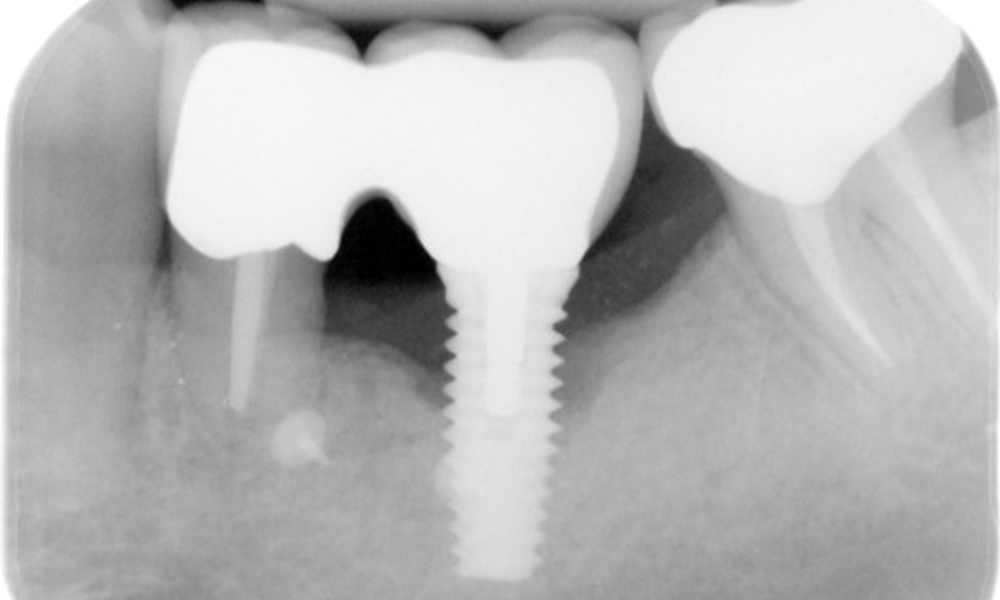

The X-ray images show the progression of bone loss.

The X-ray images show the progression of bone loss. OPG from 29.06.2020 (left) and OPG from 26.02.2024 (right).

OPG: 26/02/2024 Dental X-ray: 18/01/2024

The X-ray images show the progression of bone loss in the area of the implant in region 36: dental film from 11.02.2021 (left) and dental film from 18.01.2024 (right).

The patient has no particular risk factors with specific dental implications in his medical history. The key factor, therefore, is the requirement in terms of oral health. In this respect, there is evidence of a probing depth of 5 mm at the implant in the 3rd quadrant and, on the X-ray image, increased bone loss. The patient also has currently stable early periodontal disease and two active initial carious lesions.